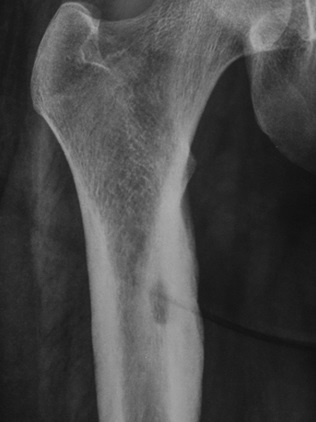

10

Q

Qual diagnóstico?

A

Lesão lítica na cortical espessada

dx: Osteoma osteóide